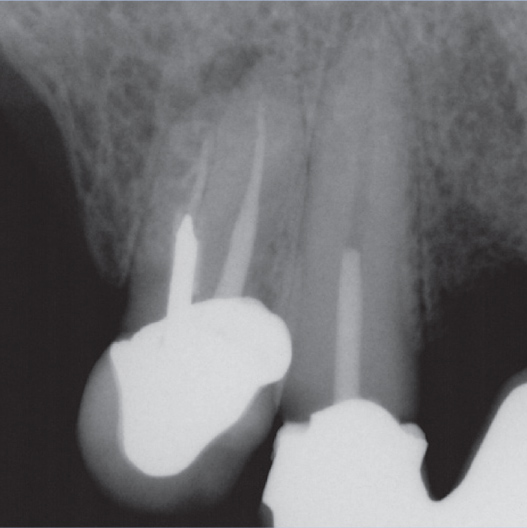

Before

Before Root Canal treatment